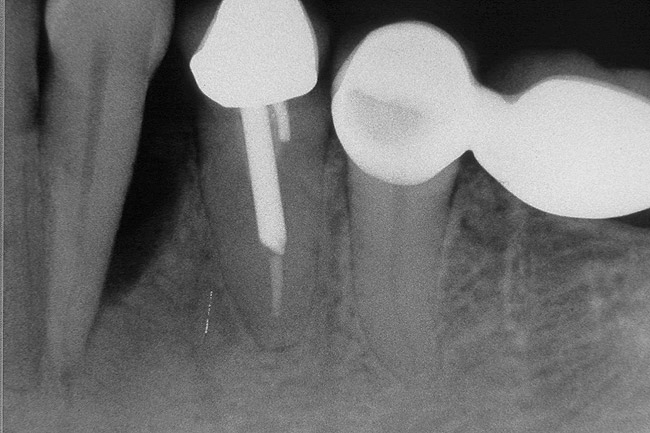

Figure 6   Tooth No. 29 with the temporary build-up close to the osseous crest. Tooth No. 29 has a short post, and tooth No. 31 has a very short root trunk.

Figure 6

Figure 7  Condition of the teeth seen in Figure 6, approximately 5 years after restoration. Note the extensive furcation involvement of tooth No. 31 and its residual periapical radiolucency.

Figure 7

Figure 8  Same case as in Figure 7 showing teeth Nos. 28 and 29. Note that tooth No. 28 was included into the four-unit restoration, and the small radiolucency on the distal tooth No. 29, which was associated with a root fracture.

Figure 8

Figure 9  Extraction of teeth Nos. 29 and 31 with immediate implants (Straumann USA, Waltham, MA) placed into the site.

Figure 9

Figure 10  Implants seen in Figure 9 restored approximately 3 months after placement.

Figure 10

The clinician also must consider the status of the adjacent teeth. Figure 6 shows teeth Nos. 29 and 31 prepared for a fixed bridge. Factors to be considered in this example were the short root of tooth No. 29 with a distal biologic width violation and a short root trunk on tooth No. 31 (which leads to furcation involvement with a small amount of facial or lingual bone loss). This patient also had periodontal disease, which further decreased the long-term prognosis of the fixed bridge option. No prospective studies directly compare the longevity of the two options: a three-unit fixed bridge vs an implant.37 Other factors that complicate comparisons of an implant vs a fixed three-unit bridge are the variability of fixed bridges as well as the variability of the implants (amount of bone, implant length, etc). For example, endodontically treated abutment teeth do not last as long as nonendodontically treated abutment teeth.38 Restorations on teeth with endodontic posts and a minimal length of ferrule do not persist as long as those on teeth without a post and at least a 2-mm ferrule.39

In a meta-analysis, three-unit fixed bridges of all kinds were found to have a success rate of ~ 84% at 60 months,40 while the single-tooth implant success rate was determined to be 95.1% at the same period. During longer study periods, the success rate of implants did not decrease nearly as much as that for fixed bridges. In a meta-analysis of nine studies, the 15-year success rate of fixed partial dentures (FPDs) was found to be about 66%, while a 20-year study of single-tooth implants had a success rate of 91%.41 In addition to the above success rates of fixed bridges, fixed bridges with more than three units have significantly lower long-term success rates than three-unit fixed bridges.42 Also, a FPD does not last as long as either an endodontically treated tooth with a single well-fitting crown or a single implant with one crown.42

In this example, the more predictable option would have been to place an implant in the No. 30 position and restore the area as three single units. However, the treatment delivered involved a four-unit fixed bridge, which then included tooth No. 28. Unfortunately, this bridge failed at approximately 5 years (Figure 7 and Figure 8) because of a root fracture of tooth No. 29 and advanced furcation involvement with residual endodontic infection of tooth No. 30. The inclusion of tooth No. 28 into the bridge also decreased its long-term prognosis because of its preparation.43 The alternative restorative option of a RPD also would decrease the prognosis of the RPD abutment teeth, which fail more often than FPD abutment teeth.43

Figure 9 shows the implant placement at the time of extraction and Figure 10 shows the implant-supported fixed bridge. In one surgical procedure, the implants in the Nos. 29 and 31 positions were placed at the time of the extraction of these two teeth. The implants were restored approximately 3 months after placement.